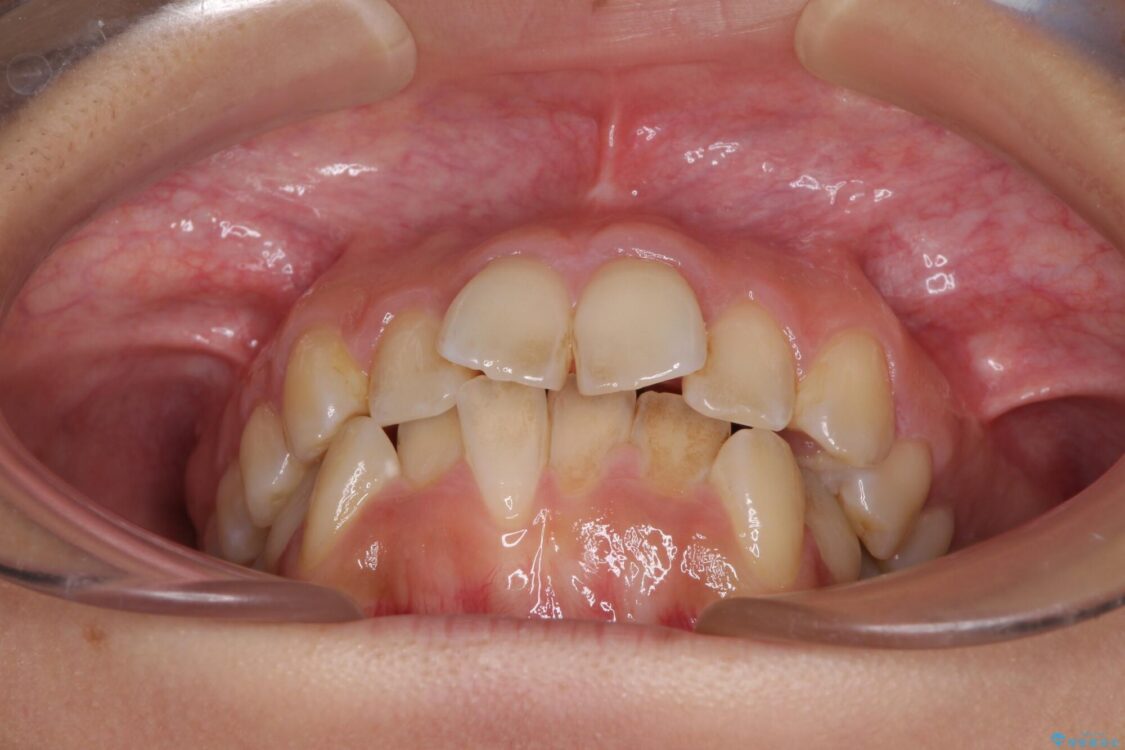

治療前

• デコボコと口元の突出感 ハーフリンガルでの抜歯矯正 治療前画像

前歯のデコボコと上顎の前突感による口の閉じにくさを気にして来院された患者様です。

目立たない装置を希望されたので、上顎が裏側装置のハーフリンガルを選択し、上下左右の小臼歯(計4歯)を抜歯して矯正治療を行うこととしました。